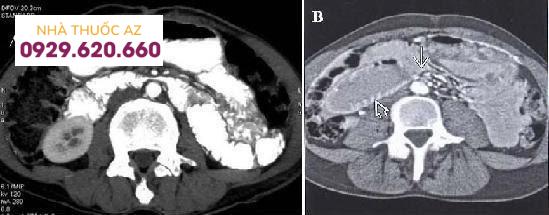

CT bụng và vùng chậu cho thấy: tá tràng bị chèn ép (mũi tên đen) giữa động mạch mạc treo tràng trên (mũi tên màu đỏ) và động mạch chủ bụng (mũi tên màu xanh).

Tá tràng bị giãn rộng (mũi tên), bị thắt đột ngột bởi động mạch mạc treo tràng trên.

Chẩn đoán hình ảnh:Tiêu chuẩn chẩn đoán hội chứng động mạch mạc treo tràng trên bao gồm:Giảm góc động mạch chủ ‐ động mạch mạc treo tràng trên tới 6‐160 (một số tác giả <22-250).Giảm khoảng cách động mạch chủ ‐ động mạch mạc treo tràng trên tới 5 ‐ 11 mm (một số tác giả <8 mm)..Siêu âm: Khảo sát được dãn dạ dày, tá tràng đến D3, thấy được vùng chuyển tiếp ở ĐMTTT và ĐM chủ bụng. Đo góc và khoảng cách ĐMTTT trên và ĐM chủ bụng.